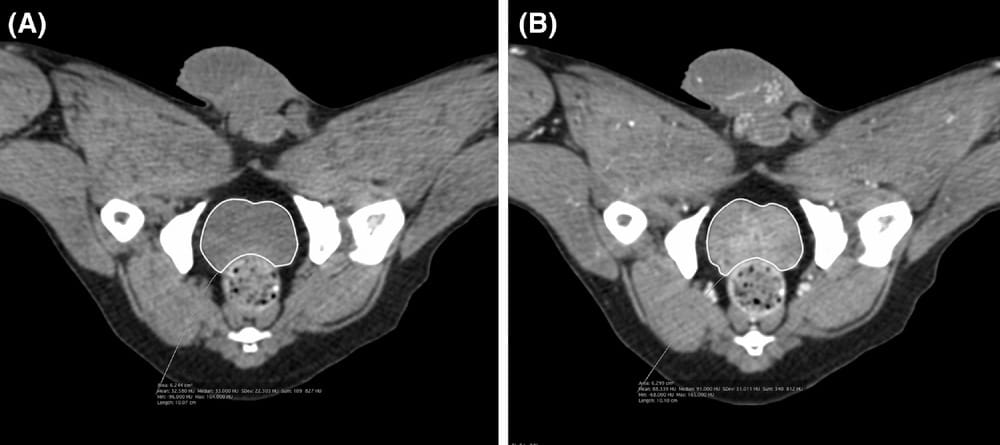

Transverse noncontrast (A) and contrast (B) computed tomography images of the pelvic area of the same dog in dorsal recumbency demonstrating prostate margins traced on images with a freehand image tracing software tool. Computed tomographic images were reconstructed with a soft tissue algorithm. A slice thickness of 0.625 mm, window level of 40 HU, and window width of 400 HU were used